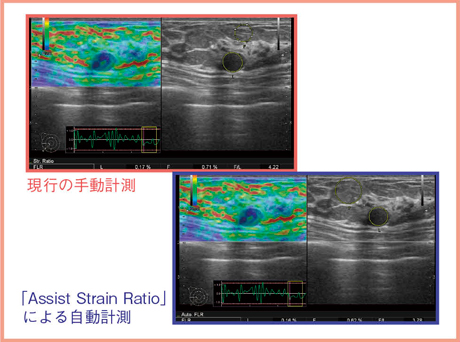

従来の手動計測では,(1)最も安定した時相でエラストグラフィをフリーズする,(2)Bモード画像上で腫瘤のROIを設定する,(3)脂肪のROIを設定すると,FLRが表示されるという複数のステップが必要となる。これに対し,Assist Strain Ratioでは,静止画でBモード画像の腫瘤の中心をワンクリックするだけでFLRの数値が表示される(図3)。

図3 Assist Strain Ratioによる自動計測

図6に,手動計測とAssist Strain Ratioによる自動計測を行った画像を示す。腫瘍のROIはほぼ同じ部分を設定しており,自動計測の脂肪のROIは手動とは場所が異なるものの,目視で脂肪と認められる部分にROIが設定されていることが確認できる。

図6 手動計測とAssist Strain Ratioの比較